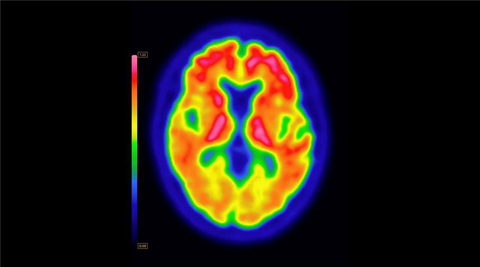

PET brain scan using Vizamyl (flutemetamol F18) with quantification software

Up to now, amyloid diagnostics such as Vizamyl have been used to provide a visual assessment of amyloid plaque accumulation in the brain. With quantification now added to the label, clinicians can reach a more objective assessment, using software that enables a calculation of amyloid load, with published research demonstrating that quantification improves diagnostic confidence and consistency among readers1,2,3. In addition, with the removal of a limitation of use for monitoring therapy effectiveness, Vizamyl can also now be used to assess whether the level of amyloid plaques has been reduced sufficiently for the therapy to potentially be stopped.

“The use of quantification in amyloid PET imaging has steadily moved from research to clinical practice, where it can aid in more confident and accurate diagnosis,” said Phillip Kuo, MD, PhD, FACR, Professor of Radiology, Section Chief of Nuclear Medicine and Director Theranostics at City of Hope National Medical Center. “Now quantification can also play a critical role in initiating and monitoring amyloid-targeted therapy for Alzheimer's disease and determining when it can be discontinued.”